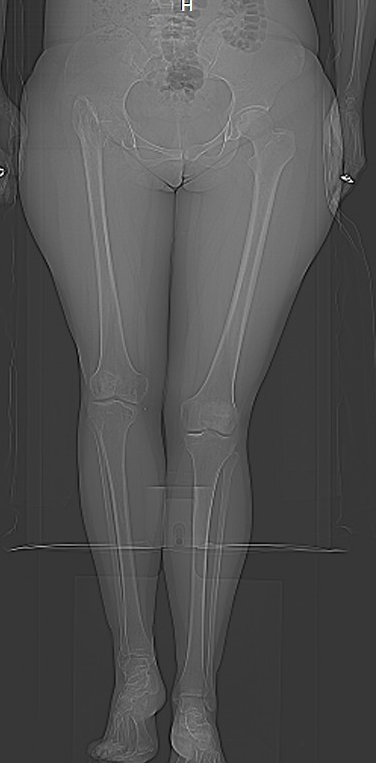

Поскольку основная жалоба на укорочение конечности, то я ей предложил удлинить голень. Величину удлинения обсудили - в пределах 4 см.

>В настоящее время: жалобы на укорочение конечности. Собирается рожать

>детей. Конечность укорочена на 7 см. Функция в правом тазобедренном

>суставе полная! Коллеги, Ваше мнение по поводу лечения?